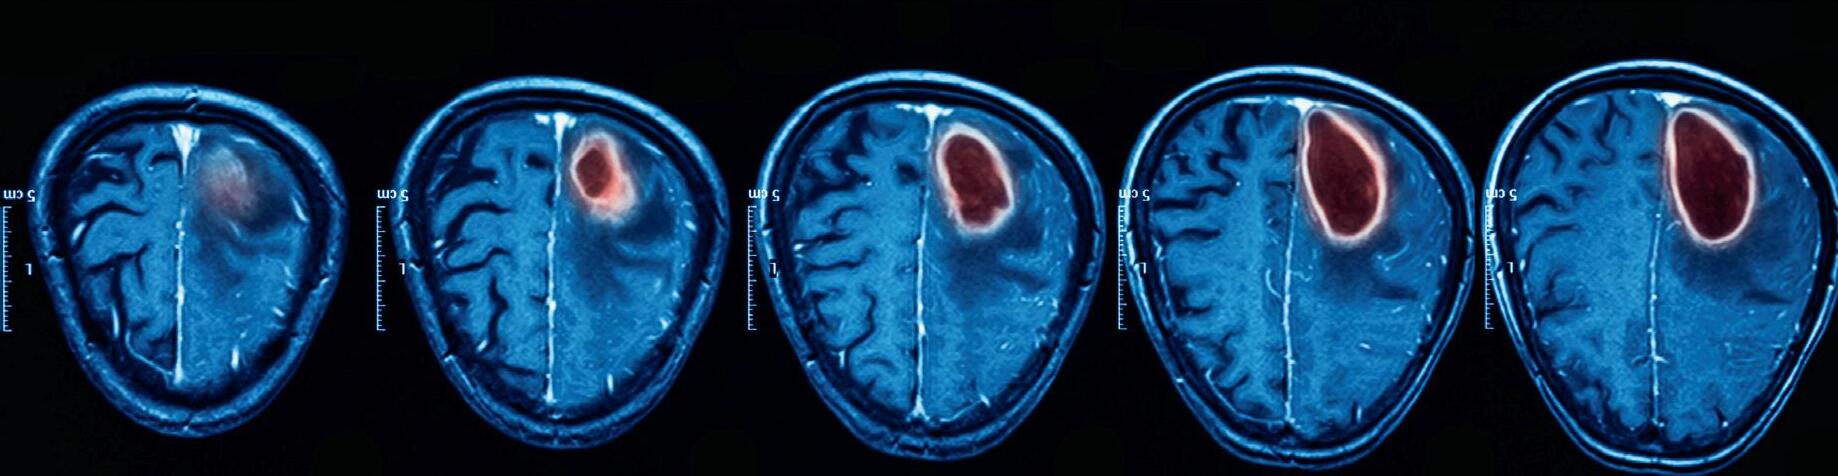

Brain structure and function is changed, so that the brains of traumatised people see the world differently. The effects of

trauma are transdiagnostic, impairing cognition and executive functioning, with a dose-related effect on mental and physical health disorders.

Technology, including functional magnetic resonance imaging (fMRI) and quantitative electroencephalography (QEEG), now enables psychiatrists to examine the organ we treat and to devise effective brain settling methods that repair brain function and heal developmental trauma.